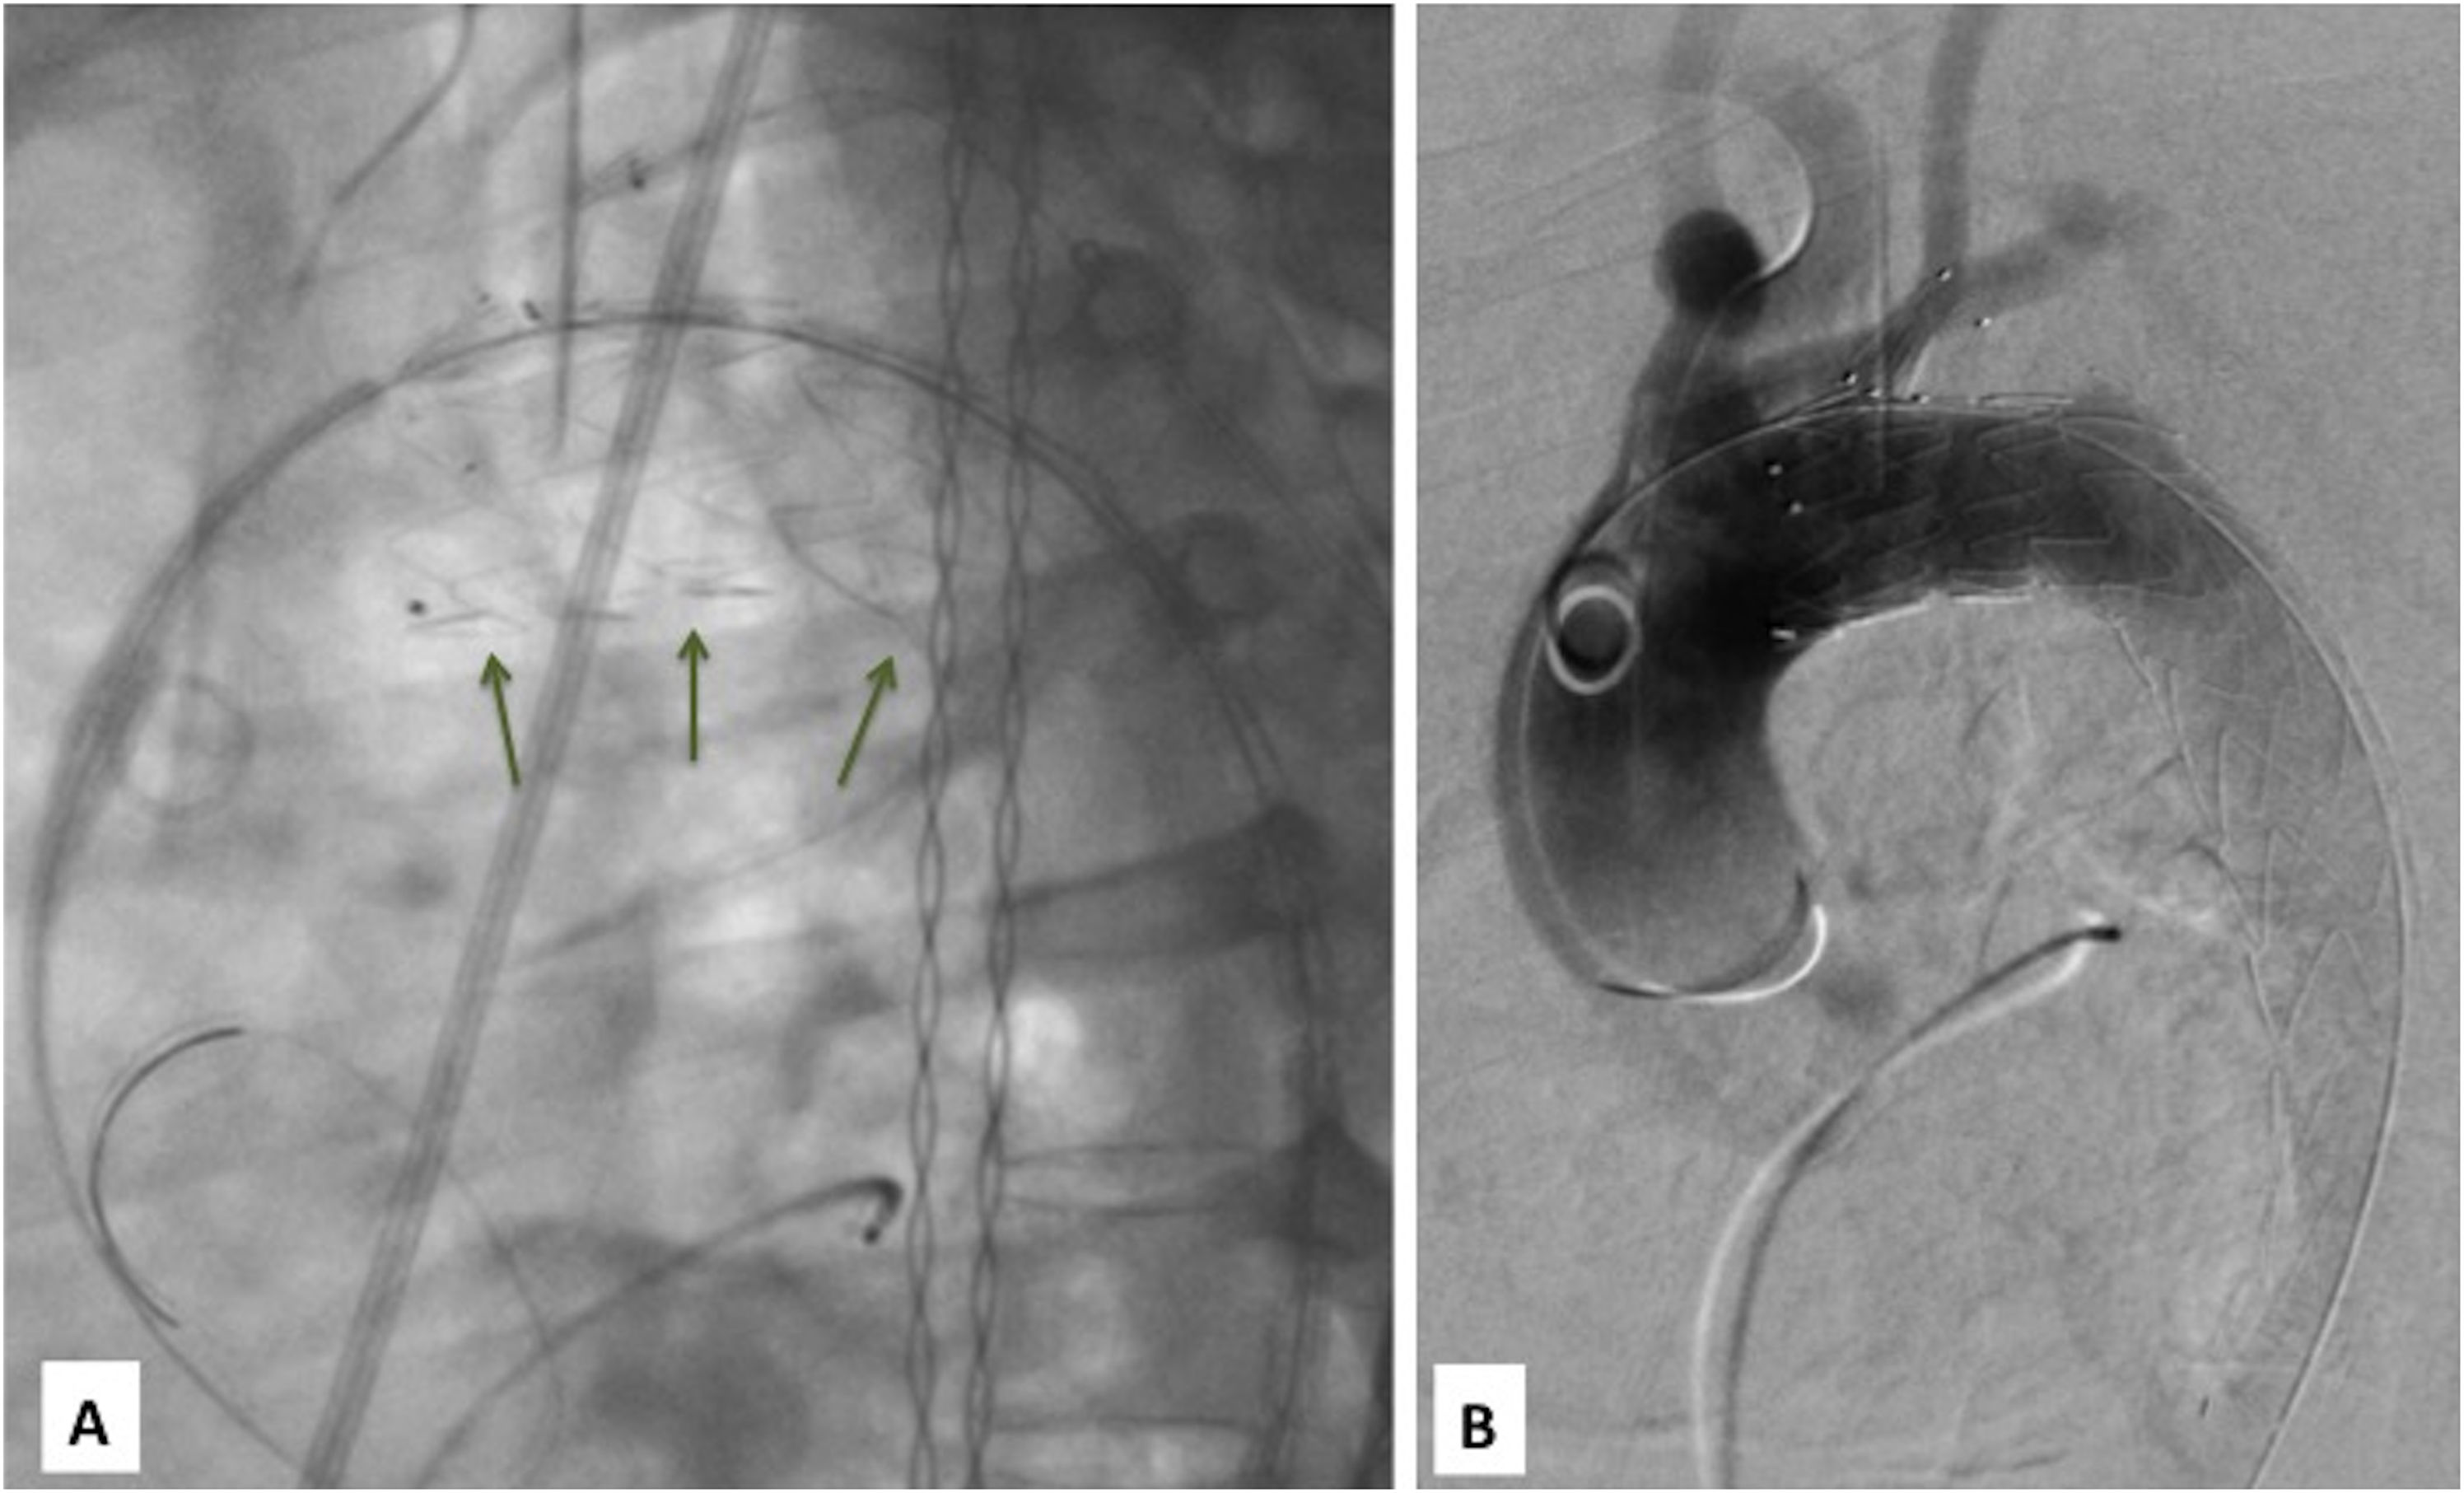

Implante paso a paso (I): A) Guías entrelazadas (2 vueltas) con flechas largas. Radiomarcador de 8 de camisa interna normoposicionado en curvatura menor con flechas cortas. B) Guías no entrelazadas, normoposición radiomarcadores de base de rama. C) Detalle ampliado de imagen B. Guías no entrelazadas con flechas largas. Radiomarcador de 8 de camisa interna normoposicionado en curvatura menor con flechas cortas. 1: radiomarcadores proximales aórticos, 2: radiomarcadores distales de rama de ASI, 3: radiomarcadores basales de rama de ASI.

Avanzar dispositivo con camisa interna (fig. 2).

Tras abrir el seguro 1.°, avanzar el dispositivo solo con la camisa interna11.

Verificar que la guía de ASI no está entrelazada en el dispositivo (a nivel de cara posterior ASI). Si estuviera entrelazada, recuperar el dispositivo hasta el introductor externo (es ligeramente costoso reintroducirlo), cerrar el seguro 1.°, y girar 360° todo el sistema a favor o en contra de agujas del reloj (tutorizando el giro con la escopia y el movimiento del puerto lateral), abrir seguro 1.° y avanzar con la camisa interna de nuevo. Si a pesar de ello sigue entrelazada, hacer 2 giros de 360° contraria a la dirección que tomamos antes. Si ya no entrelazada, pasar a siguiente paso.

Verificar en cara posterior ASI normoposición de los radiomarcadores de la base de la rama ASI. Si todos están por encima de la Lunderquist® se puede aceptar, no obstante, si todos los marcadores estuvieran en la misma línea sería la situación de máxima alineación. Si no es así, hacemos la misma maniobra del punto anterior en ATD, pero con pequeños giros de 30-90° para buscar la posición correcta.

Pull & Through (fig. 3). Tras abrir seguro 2.°, primero se inicia retirada (PULL) de unos 2-4cm de la camisa interna, en dicho momento simultáneamente se sigue con esta maniobra hasta el final mientras se avanza de forma concomitante la prótesis/cánula interna (Through) de forma que la rama va entrando en la ASI y la cabeza aórtica avanza hacia su landing proximal.